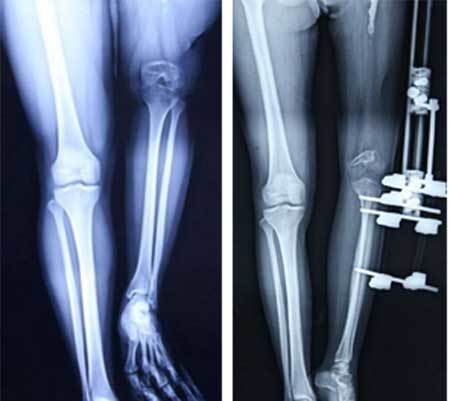

| Xu đã đeo bộ y cụ thép chuyên dụng suốt 1 năm trời để kéo dài chân trái thêm 23cm. Ảnh: Rex |

Trong đó, để kéo dài chân, các bác sĩ đã lắp một bộ khung kim loại vào chân trái của Xu và mỗi ngày cô phải vặn ốc vít để kéo dài chân thêm một chút. Tiến sĩ Hu giải thích: "Sau phẫu thuật, mỗi ngày bệnh nhân Xu cần phải điều chỉnh thiết bị bánh răng nhằm kéo dài chân trái thêm 1mm. Quá trình kéo dài phải diễn ra rất chậm, do các dây thần kinh và tế bào cần thời gian để giãn rộng. Nếu quá trình diễn ra quá nhanh, các dây thần kinh hoặc tế bào có thể đứt gãy, gây ra chứng liệt vĩnh viễn".

| Kết quả là 2 chân của Xu (phải) hiện đã đều nhau, giúp cô có thể đi lại như người bình thường. Ảnh: Rex |

Cô Xu đã mất 1 năm trời ròng rã kéo dài chân trước khi được phẫu thuật thay thế đầu gối và khớp háng trái nhân tạo vào tháng 10/2013. Quá trình điều trị cho cô cuối cùng đã hoàn tất vào tháng 2 năm nay. Theo các bác sĩ, sau một vài tháng hồi phục nữa, Xu sẽ có thể đi lại như người bình thường.